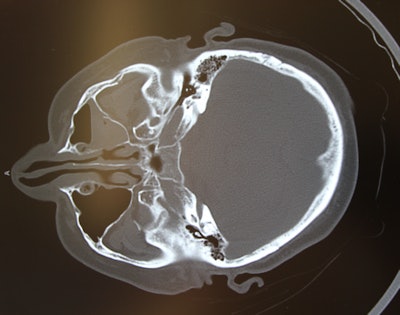

For example, say the surgeon is placing a mesh implant to reconstruct an orbital floor fracture, and he or she notices in the intraoperative CT images that the placement is slightly off. Maybe the contour of the orbit doesn't precisely mirror the other side of the face.

Portable scanners were used, along with MDCT, which provides the best image resolution, and cone-beam CT, which delivers exceptionally low radiation doses in the 40 µSv to 80 µSv range (versus 400 µSv to 800 µSv for MDCT).

In the study, surgeons notified the radiology department the morning of surgery, and the technologists warmed up the scanner and placed it just outside of the operating room prior to surgery. A C-arm drape was placed over the patient before the scanner was positioned over the patient's head, the authors explained. The scanner and drape were removed while the surgeons formatted and read the scans to prepare the patient for wound closure or revision, as indicated by imaging.

The eight complex cases with intraoperative revisions included five orbital reconstructions, one panfacial fracture, two orbitozygomatic fractures, and one orbitozygomatic tumor reconstruction. Among the nine patients who had intraoperative revisions, three underwent repeat scanning to verify final placement of the implant, including two who were undergoing complicated secondary orbital reconstructions.